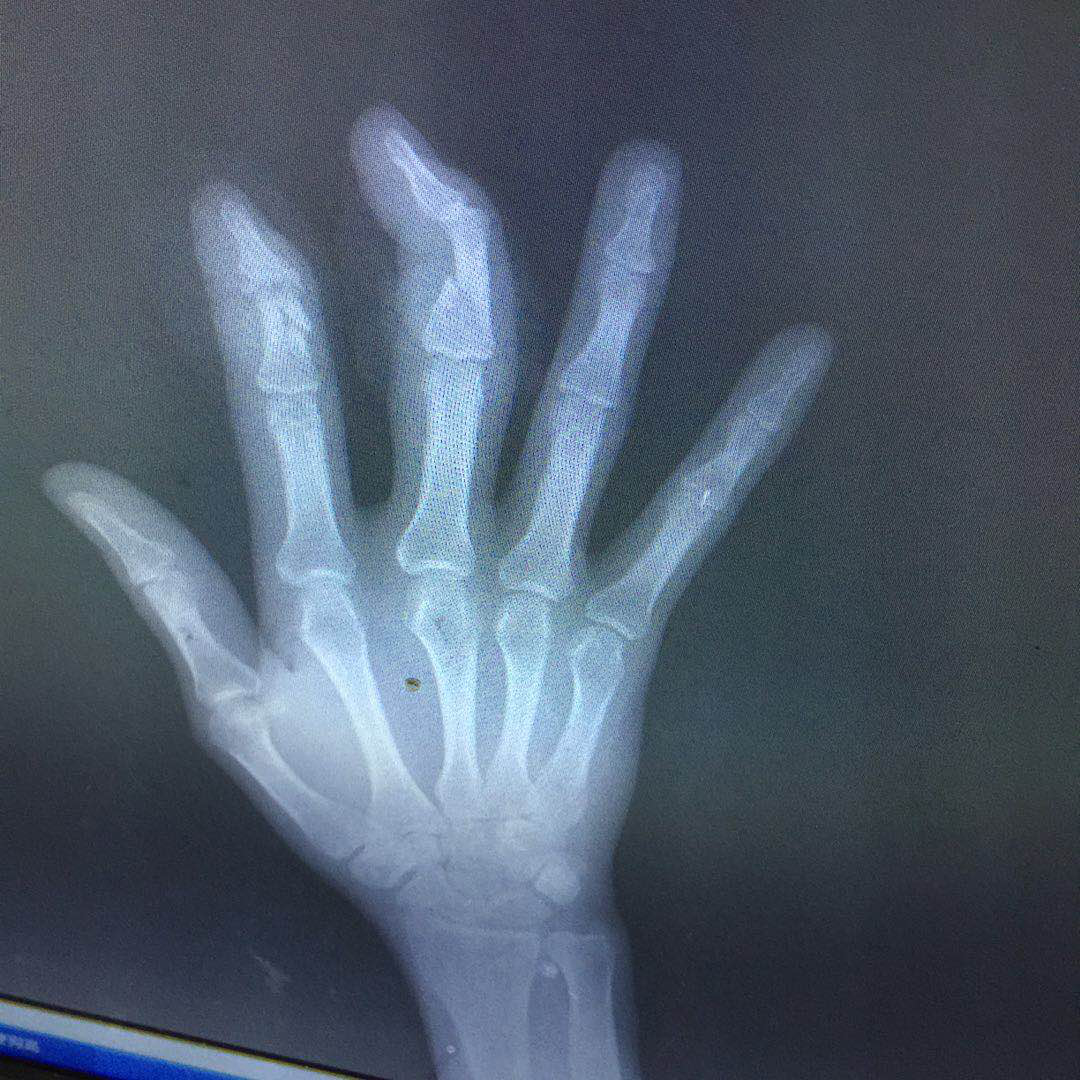

近日,我院收治一例手外伤患者,该患者于3月23日14:30左右在工作中被机器压伤右手致疼痛流血,自行按压止血后,立即由同事送到我院就诊,DR检查结果示:右手示指中节远端粉碎性骨折、中指中节骨折。随后我院立刻安排手术,副院长兼手外科主任邱庆明和张羊城医生主刀,对患者伤指进行血管神经肌腱探查修复、骨折内固定、清创。手术顺利,目前患者在我院接受后续康复治疗中。